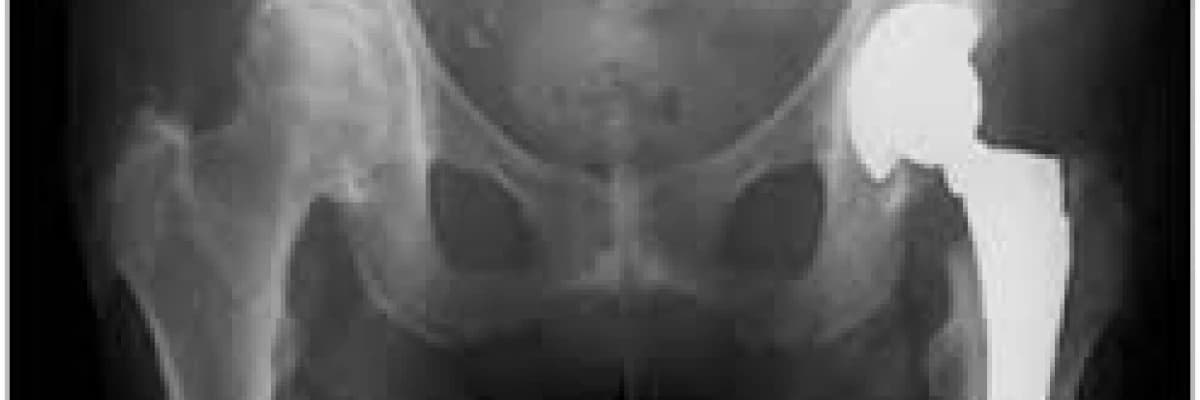

Total kalça protezi rehabilitasyonu

Kalça protezi iki farklı şekilde kemiğe tutturulur. İleri yaştaki, kemik kalitesi zayıf olan hastalara sement (çimento) ile dolgu yapılarak kaynama sağlanırken, daha genç ve kemik kalitesi iyi olan hastada sementsiz (çimentosuz) sabitleme yapılarak, kemiğin kendi kendine dolması beklenir.